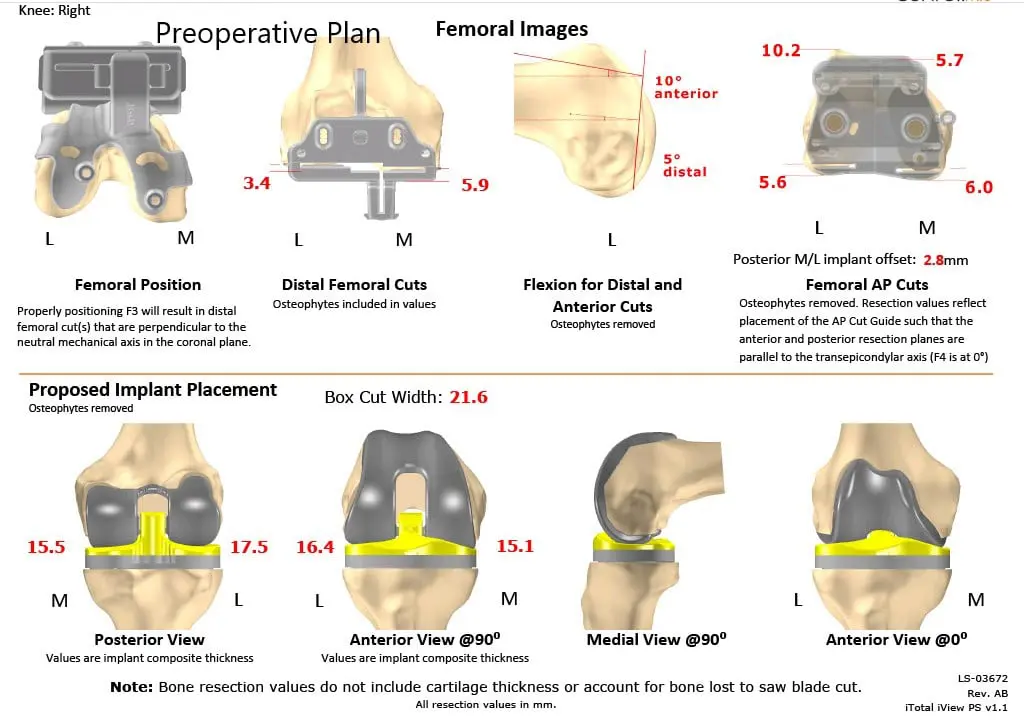

As a part of the preparation of the custom implants, a preoperative CT was obtained a few weeks prior to surgery. The results were utilized to create 3D images of the patient’s unique anatomy. Customized implants were then made along with disposable custom instruments. A preoperative plan was formalized to aid the surgery in precision cuts and alignment.

Complete Orthopedics patient-specific surgical plan for a right custom knee replacement in a 59-year-old male (scan 2)